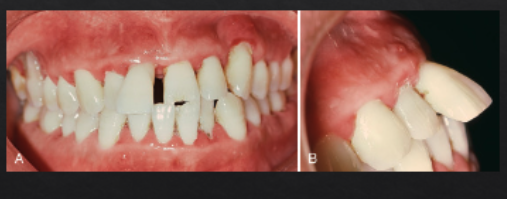

what are clinical signs of pathologic tooth migration (a form of secondary occlusal trauma)?

periodontitis

increased mobility

new interproximal gaps

tooth extrusion

pathologic tooth migration is generally a sign of mild/moderate/severe advanced disease

severe